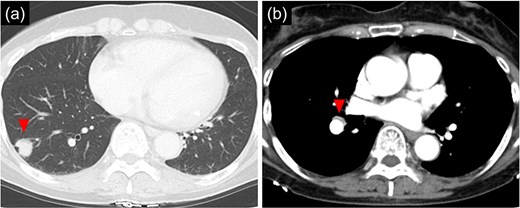

The patient was a 66 year-old woman with no history of smoking or other medical history. Chest CT showed an 18 mm nodule suspected to be a primary lung cancer in the S9 region of the right lower lobe (Fig. 1). CT-guided lung biopsy revealed lung adenocarcinoma. PET/CT showed FDG accumulation in #11i lymph node suspicious for metastasis, and the preoperative staging was c-T1bN1M0 Stage IIB. The patient was referred to the Department of Thoracic Surgery in our hospital. In addition, a 9 mm size BD communicating with the right main bronchus was observed below the tracheal bifurcation in the preoperative image (Fig. 2). Right lower lobectomy and mediastinal lymph node dissection were planned; however, because the inferior mediastinal tissue was to be dissected, a procedure for BD was also considered necessary. To achieve safe dissection around the BD, robotic thoracoscopic surgery was planned, taking advantage of the fine movement and highly flexible forceps manipulation.

(a) 9 mm size bronchial diverticulum located at the subcarinal region. (b) Bronchial diverticulum opening in the right main bronchus and two rings distal to the carina.

Bronchoscopy after intubation revealed an orifice of the BD in the cartilage of the right main bronchus with two rings below the carina (Fig. 2). First, a lower mediastinal lymph node dissection and BD were performed. The area around the BD was prone to bleeding and the lymph nodes were in close contact with each other (Fig. 3), making it difficult to separate them from the BD. After identifying and exposing the stalk of a BD, ligation of the diverticulum with ENDOLOOP® PDS II Ligature allowed for control of bleeding and the lymph nodes could be safely removed from the BD (Video 1).